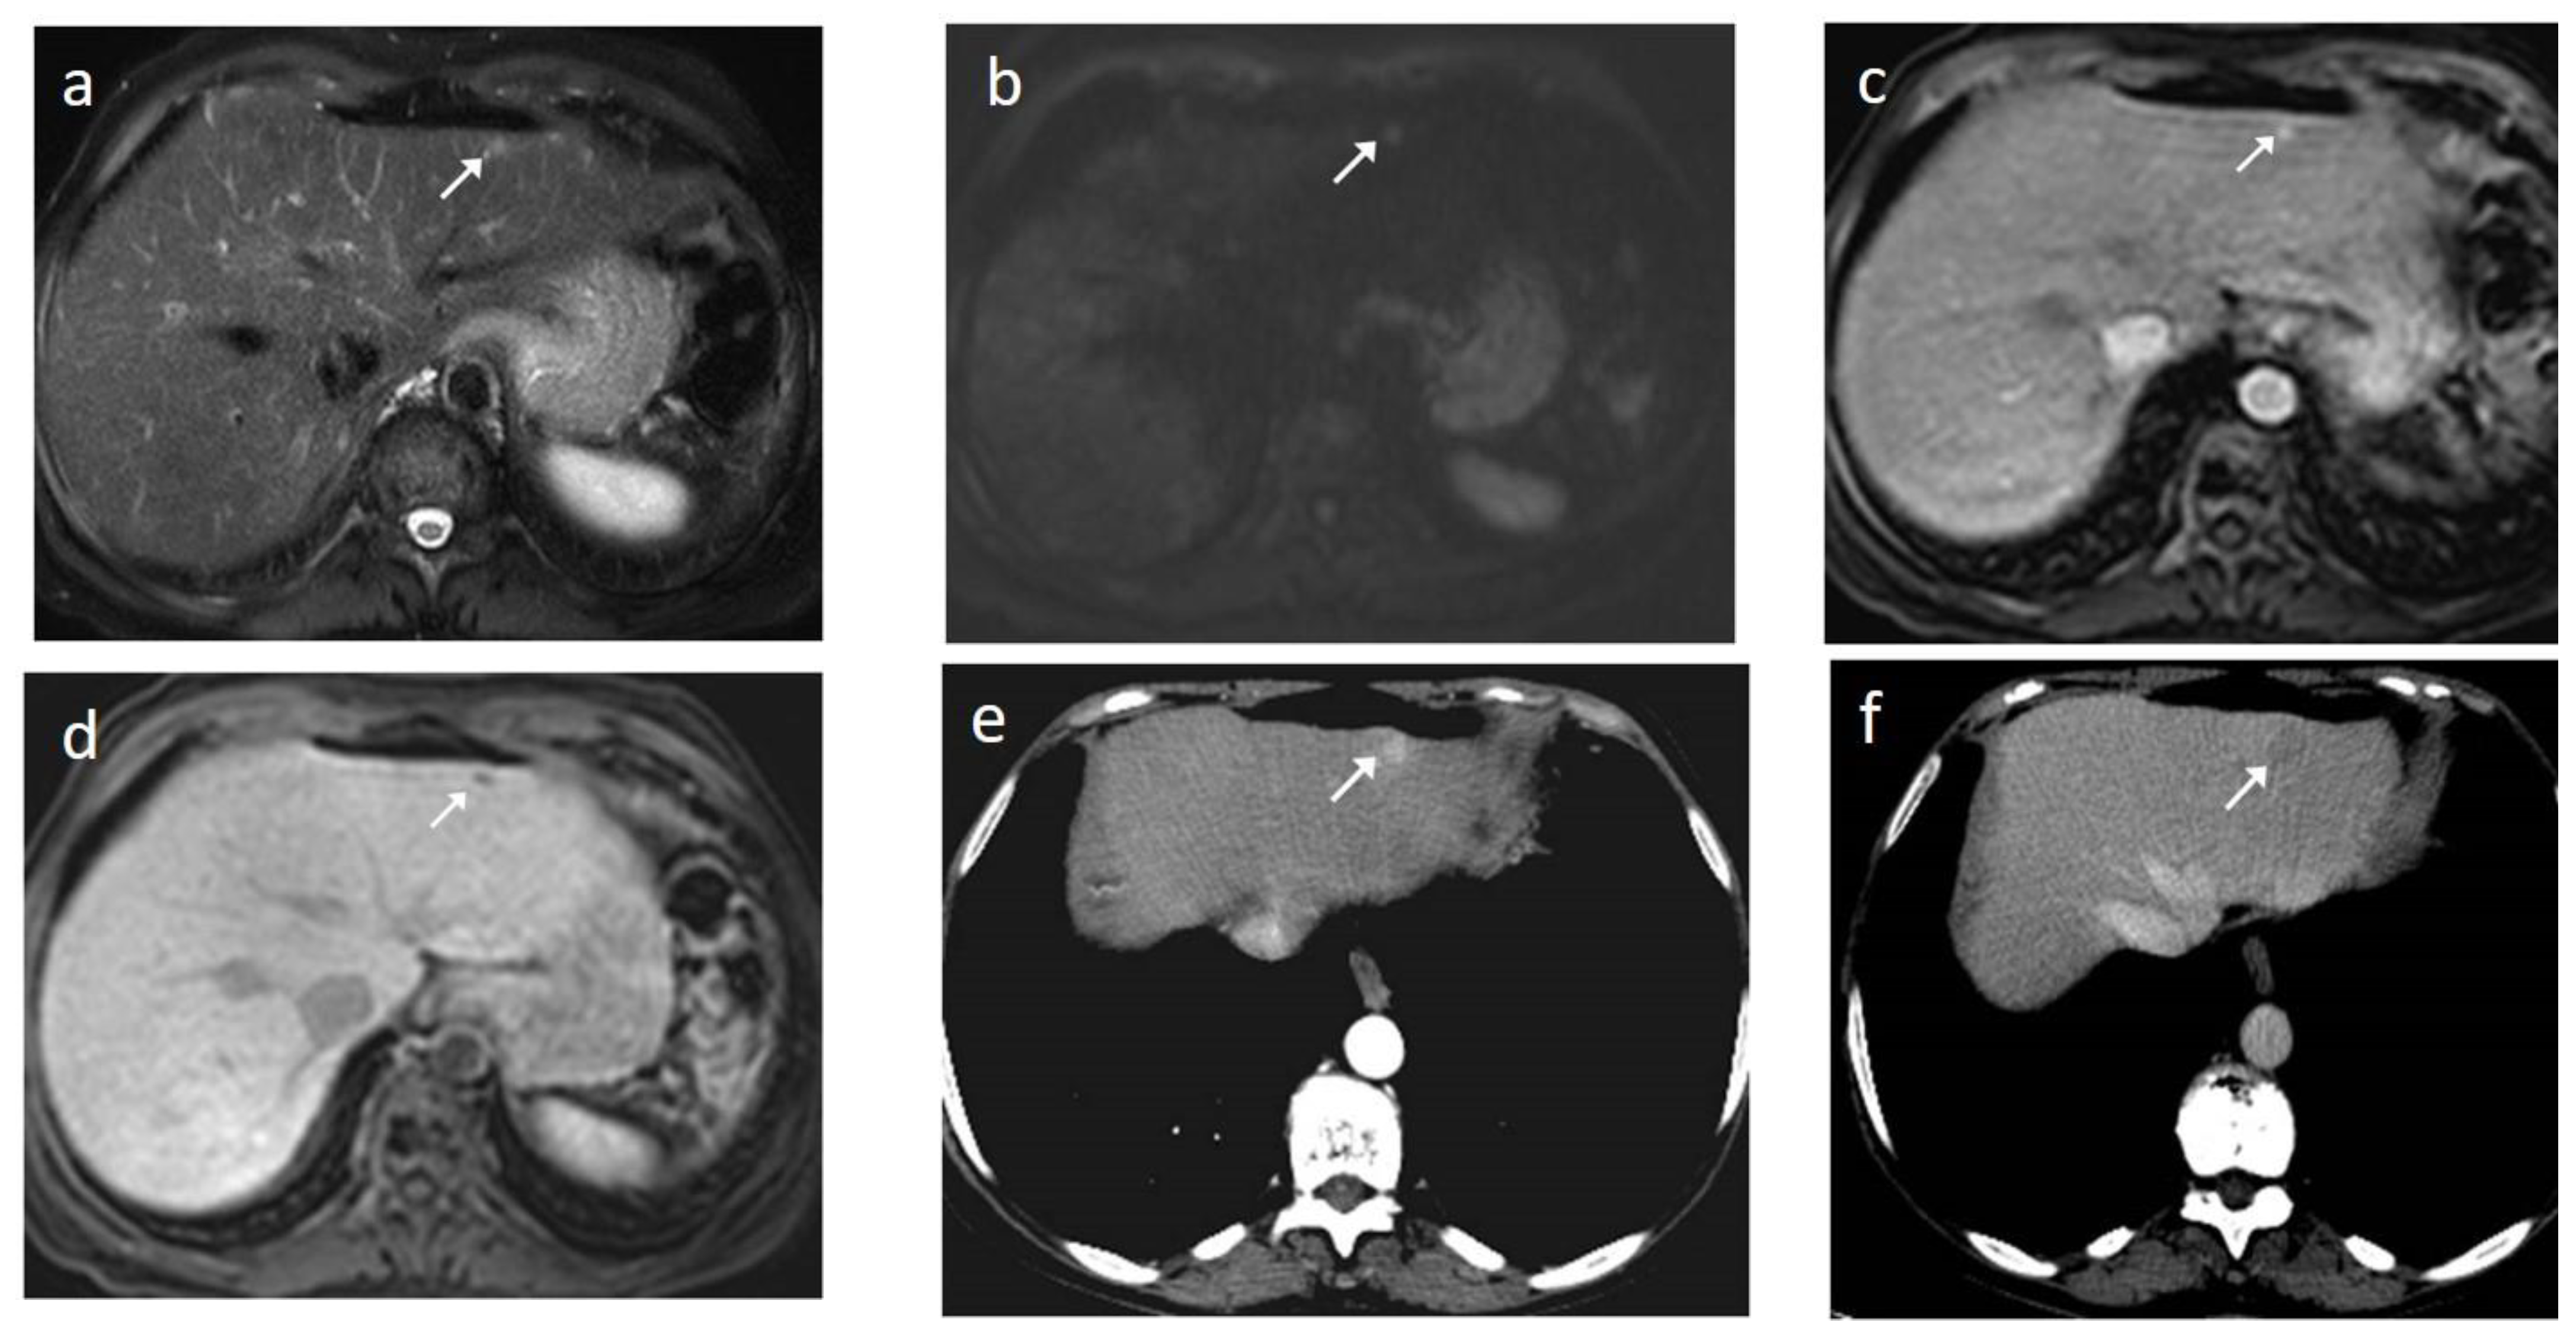

3. Contrast-Enhanced Ultrasound

- Kim, Y.K.; Lee, W.J.; Park, M.J.; Kim, S.H.; Rhim, H.; Choi, D. Hypovascular Hypointense Nodules on Hepatobiliary Phase Gadoxetic Acid–enhanced MR Images in Patients with Cirrhosis: Potential of DW Imaging in Predicting Progression to Hypervascular HCC. Radiology 2012, 265, 104–114. [Google Scholar] [CrossRef] [PubMed]

- Kim, Y.K.; Kim, C.S.; Han, Y.M.; Lee, Y.H. Detection of liver malignancy with gadoxetic acid-enhanced MRI: Is addition of diffusion-weighted MRI beneficial? Clin. Radiol. 2011, 66, 489–496. [Google Scholar] [CrossRef] [PubMed]

- Piana, G.; Trinquart, L.; Meskine, N.; Barrau, V.; Beers, B.V.; Vilgrain, V. New MR imaging criteria with a diffusion-weighted sequence for the diagnosis of hepatocellular carcinoma in chronic liver diseases. J. Hepatol. 2011, 55, 126–132. [Google Scholar] [CrossRef]

- Park, M.J.; Kim, Y.K.; Lee, M.W.; Lee, W.J.; Kim, Y.-S.; Kim, S.H.; Choi, D.; Rhim, H. Small Hepatocellular Carcinomas: Improved Sensitivity by Combining Gadoxetic Acid–enhanced and Diffusion-weighted MR Imaging Patterns. Radiology 2012, 264, 761–770. [Google Scholar] [CrossRef]

- Park, M.-S.; Kim, S.; Patel, J.; Hajdu, C.H.; Do, R.K.G.; Mannelli, L.; Babb, J.; Taouli, B. Hepatocellular carcinoma: Detection with diffusion-weighted versus contrast-enhanced magnetic resonance imaging in pretransplant patients. Hepatology 2012, 56, 140–148. [Google Scholar] [CrossRef]

- Kitao, A.; Matsui, O.; Yoneda, N.; Kozaka, K.; Shinmura, R.; Koda, W.; Kobayashi, S.; Gabata, T.; Zen, Y.; Yamashita, T.; et al. The uptake transporter OATP8 expression decreases during multistep hepatocarcinogenesis: Correlation with gadoxetic acid enhanced MR imaging. Eur. Radiol. 2011, 21, 2056–2066. [Google Scholar] [CrossRef] [PubMed]